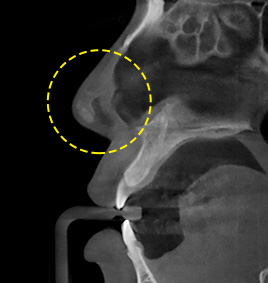

กรณีที่ 2จมูกงุ้มและคดตรงกลาง

ตัดกระดูกและกระดูกอ่อนอย่างเหมาะสมขึ้นอยู่กับระดับความคด